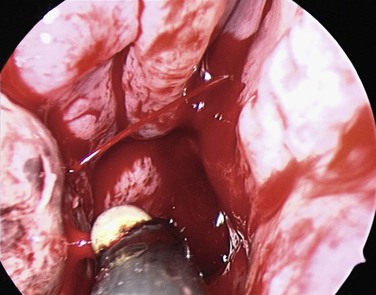

If bleeding cannot be controlled after endoscopic examination and cautery and/or nasal packing, sedation and examination under a local or general anesthetic are indicated. Bipolar diathermy of any bleeding points or ESPAL is then the treatment of choice.10 Clipping or diathermy of the sphenopalatine artery is currently the accepted treatment for management of persistent posterior epistaxis,50,62,68-72 because it produces less morbidity compared with embolization or ligation of the maxillary or external carotid artery.73,74 The main complication in 25% of patients was nasal crusting. Pooled case series data have shown that 98% of patients had epistaxis controlled by clipping or diathermy of the sphenopalatine artery.75 The endoscopic sinus surgeon should locate the sphenopalatine artery at the level of the ethmoid crest (Fig. 42-17).75 An incision is made over the posterior fontanelle, a submucosal flap is lifted, and the anterior branch is identified with its origin just posterior to the crista ethmoidalis. The anterior branch is then identified and is either clipped or diathermied (Fig. 42-18). In the majority of cases, the sphenopalatine foramen opens into the middle and superior meatus.

The sphenopalatine artery normally starts to branch lateral to the ethmoid crest, and these branches vary widely. It is important that the surgeon who undertakes ligation or cautery of the artery is aware that over 97% of individuals have two or more branches medial to the ethmoid crest, 67% have three or more branches, and 35% have four or more branches. The endoscopic sinus surgeon views the sphenopalatine artery at the level of the sphenopalatine foramen or a few millimeters medial to it. Making a mucosal incision in the posterior fontanelle area, anterior to the horizontal part of the base of the middle turbinate as it joins the lateral nasal wall, a submucosal flap is lifted, and the artery is identified posterior to the crista ethmoidalis and is clipped. Some authors describe identifying the artery and clipping it, but they did not dissect more to verify whether any other branches were present.68,71,72 It may be because of the mistaken belief that the artery enters as a single trunk into the nose, which has led to failure of these procedures. One study specifically looked at the branching pattern of this artery from the endoscopic surgeon's point of view.51,76 They found two branches of the sphenopalatine artery near the sphenopalatine foramen. In their study, 16% branched within the foramen and reached the nose together; in 42% the branches had an anteroposterior relationship, with the septal branch being posterior to the posterior nasal branch, and in the remaining 42%, the septal branch exited through a separate foramen posterior to the sphenopalatine foramen.51

In a study by Simmen and colleagues,76 they found that over 97% of specimens had two or more branches medial to the crista ethmoidalis, 30% had three branches, and in one specimen, 10 branches were identified. The variation in 77 specimens is illustrated in Figure 42-19.

Various reports have claimed the success rate of ESPAL to be between 92% and 100% in controlling epistaxis with this technique.69,71,75 Failure to clip all the branches of the sphenopalatine artery may be the reason for continued epistaxis after the procedure. All divisions of the sphenopalatine artery occur in the pterygomaxillary fissure and enter the nasal fossa as separate blood vessels. The arrangement of these branches in relation to the sphenopalatine foramen varies widely. The largest and most anteriorly based branch is the posterior lateral nasal branch, which must be clipped and divided so that the flap can be lifted superiorly to locate the nasopalatine branch, which must be clipped and divided as well. Because such wide variations are found in the branching pattern of the sphenopalatine artery, careful dissection is required even after these two branches are clipped. A thorough search by careful dissection should be done all around the sphenopalatine foramen to find any other branches that can be clipped. Clipping or diathermy of the sphenopalatine artery has a 0% to 8% failure rate75 and is not associated with any serious complications. The main complication, as previously mentioned, is failure to control epistaxis, and it is usually due to failure to clip all the branches of the sphenopalatine artery. The arrangements of these branches are unpredictable, as seen in our study, and can vary between sides in the same individual. In addition, the branches of this artery can come out through separate foramina, and if the surgeon is not aware of this, it can result in missing a few branches. Other complications are uncommon and include nasal crusting, palatal numbness, acute sinusitis, decreased lacrimation, and septal perforation.71 A long-term study of ESPAL showed a 93% success rate.77 We do not advocate packing and repacking for refractory epistaxis if this can be avoided.